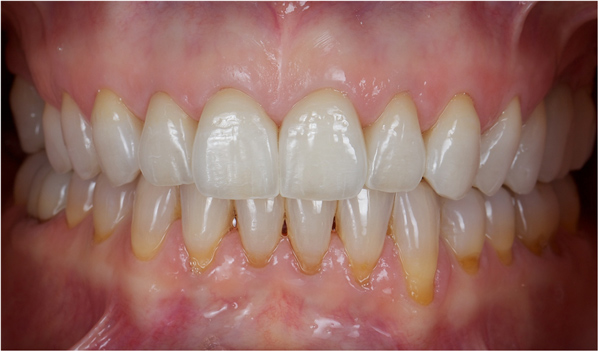

Figure 26 The healthy periodontal and dental implant foundation and gingival symmetry set the framework for the completion of the lithium-disilicate all-ceramic restorations.

Figure 26

Figure 27 The healthy periodontal and dental implant foundation and gingival symmetry set the framework for the completion of the lithium-disilicate all-ceramic restorations.

Figure 27

Once the healing was complete for the periodontal and dental implant procedures (Figure 22 and Figure 23), the final tooth preparations were completed and final impressions were made; records, including the electronic pantographic record, were then obtained. The treatment wax was used (Figure 24) to secure the patient’s approval of the esthetic design and to evaluate the esthetics and plan for the final prosthesis, including the cross-bite. The vertical dimension was raised, the facial anatomy was checked, and her speech and esthetics were checked by filming the patient and viewing facial profiles. Next, the implant abutments were made (Figure 25). In this case, metal–ceramic abutments were chosen; they were tried on before beginning the fabrication of the final restorations. These monolithic ceramic materials use lithium disilicate, which can result in a restoration with excellent biomechanical and esthetic properties (Figure 26 and Figure 27). The restorations were observed; the radiographs show the implants placed in the regenerated bone (Figure 28).